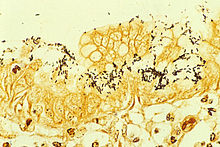

Colonization of the stomach by H. pylori results in chronic gastritis, an inflammation of the stomach lining. The severity of the inflammation is likely to underlie H. pylori-related diseases. Duodenal and stomach ulcers result when the consequences of inflammation allow the acid and pepsin in the stomach lumen to overwhelm the mechanisms that protect the stomach and duodenal mucosa from these caustic substances. The type of ulcer that develops depends on the location of chronic gastritis, which occurs at the site of H. pylori colonization. The acidity within the stomach lumen affects the colonization pattern of H. pylori, and therefore ultimately determines whether a duodenal or gastric ulcer will form. In people producing large amounts of acid, H. pylori colonizes the antrum of the stomach to avoid the acid-secreting parietal cells located in the corpus (main body) of the stomach. The inflammatory response to the bacteria induces G cells in the antrum to secrete the hormone gastrin, which travels through the bloodstream to the corpus. Gastrin stimulates the parietal cells in the corpus to secrete even more acid into the stomach lumen. Chronically increased gastrin levels eventually cause the number of parietal cells to also increase, further escalating the amount of acid secreted. The increased acid load damages the duodenum, and ulceration may eventually result. In contrast, gastric ulcers are often associated with normal or reduced gastric acid production, suggesting the mechanisms that protect the gastric mucosa are defective. In these patients, H. pylori can also colonize the corpus of the stomach, where the acid-secreting parietal cells are located. However chronic inflammation induced by the bacteria causes further reduction of acid production and, eventually, atrophy of the stomach lining, which may lead to gastric ulcer and increases the risk for stomach cancer.

Colonization with H. pylori is not a disease in and of itself but a condition associated with a number of disorders of the upper gastrointestinal tract. Testing for H. pylori is recommended if there is peptic ulcer disease, low grade gastric MALT lymphoma, after endoscopic resection of early gastric cancer, if there are first degree relatives with gastric cancer, and in certain cases of dyspepsia, not routinely. Several ways of testing exist. One can test noninvasively for H. pylori infection with a blood antibody test, stool antigen test, or with the carbon urea breath test (in which the patient drinks 14C—or 13C-labelled urea, which the bacterium metabolizes, producing labelled carbon dioxide that can be detected in the breath). However, the most reliable method for detecting H. pylori infection is a biopsy check during endoscopy with a rapid urease test, histological examination, and microbial culture. There is also a urine ELISA test with a 96% sensitivity and 79% specificity. None of the test methods is completely failsafe. Even biopsy is dependent on the location of the biopsy. Blood antibody tests, for example, range from 76% to 84% sensitivity. Some drugs can affect H. pylori urease activity and give false negatives with the urea-based tests.